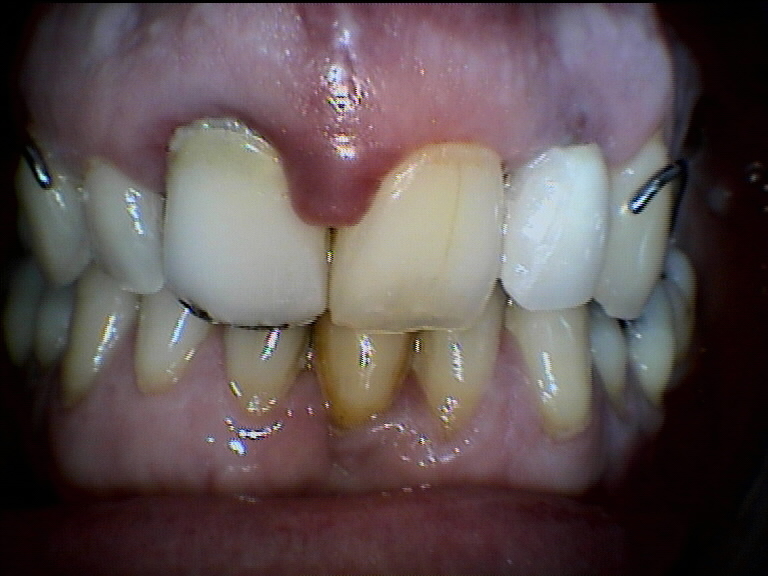

Paziente di 45 anni che si presenta per una parodontite che ha implicazioni anche estetiche.

Dopo una prima serie di levigature radicolari e una corona in porcellana dell’incisivo superiore di destra e in seguito anche di quello di sinistra, la situazione è decisamente migliorata, anche se necessitano ancora delle sedute di perfezionamento.

E’ stato anche sostituito un incisivo laterale superiore sinistro, che era affidato ad un apparecchio mobile, con un impianto osteointegrato.